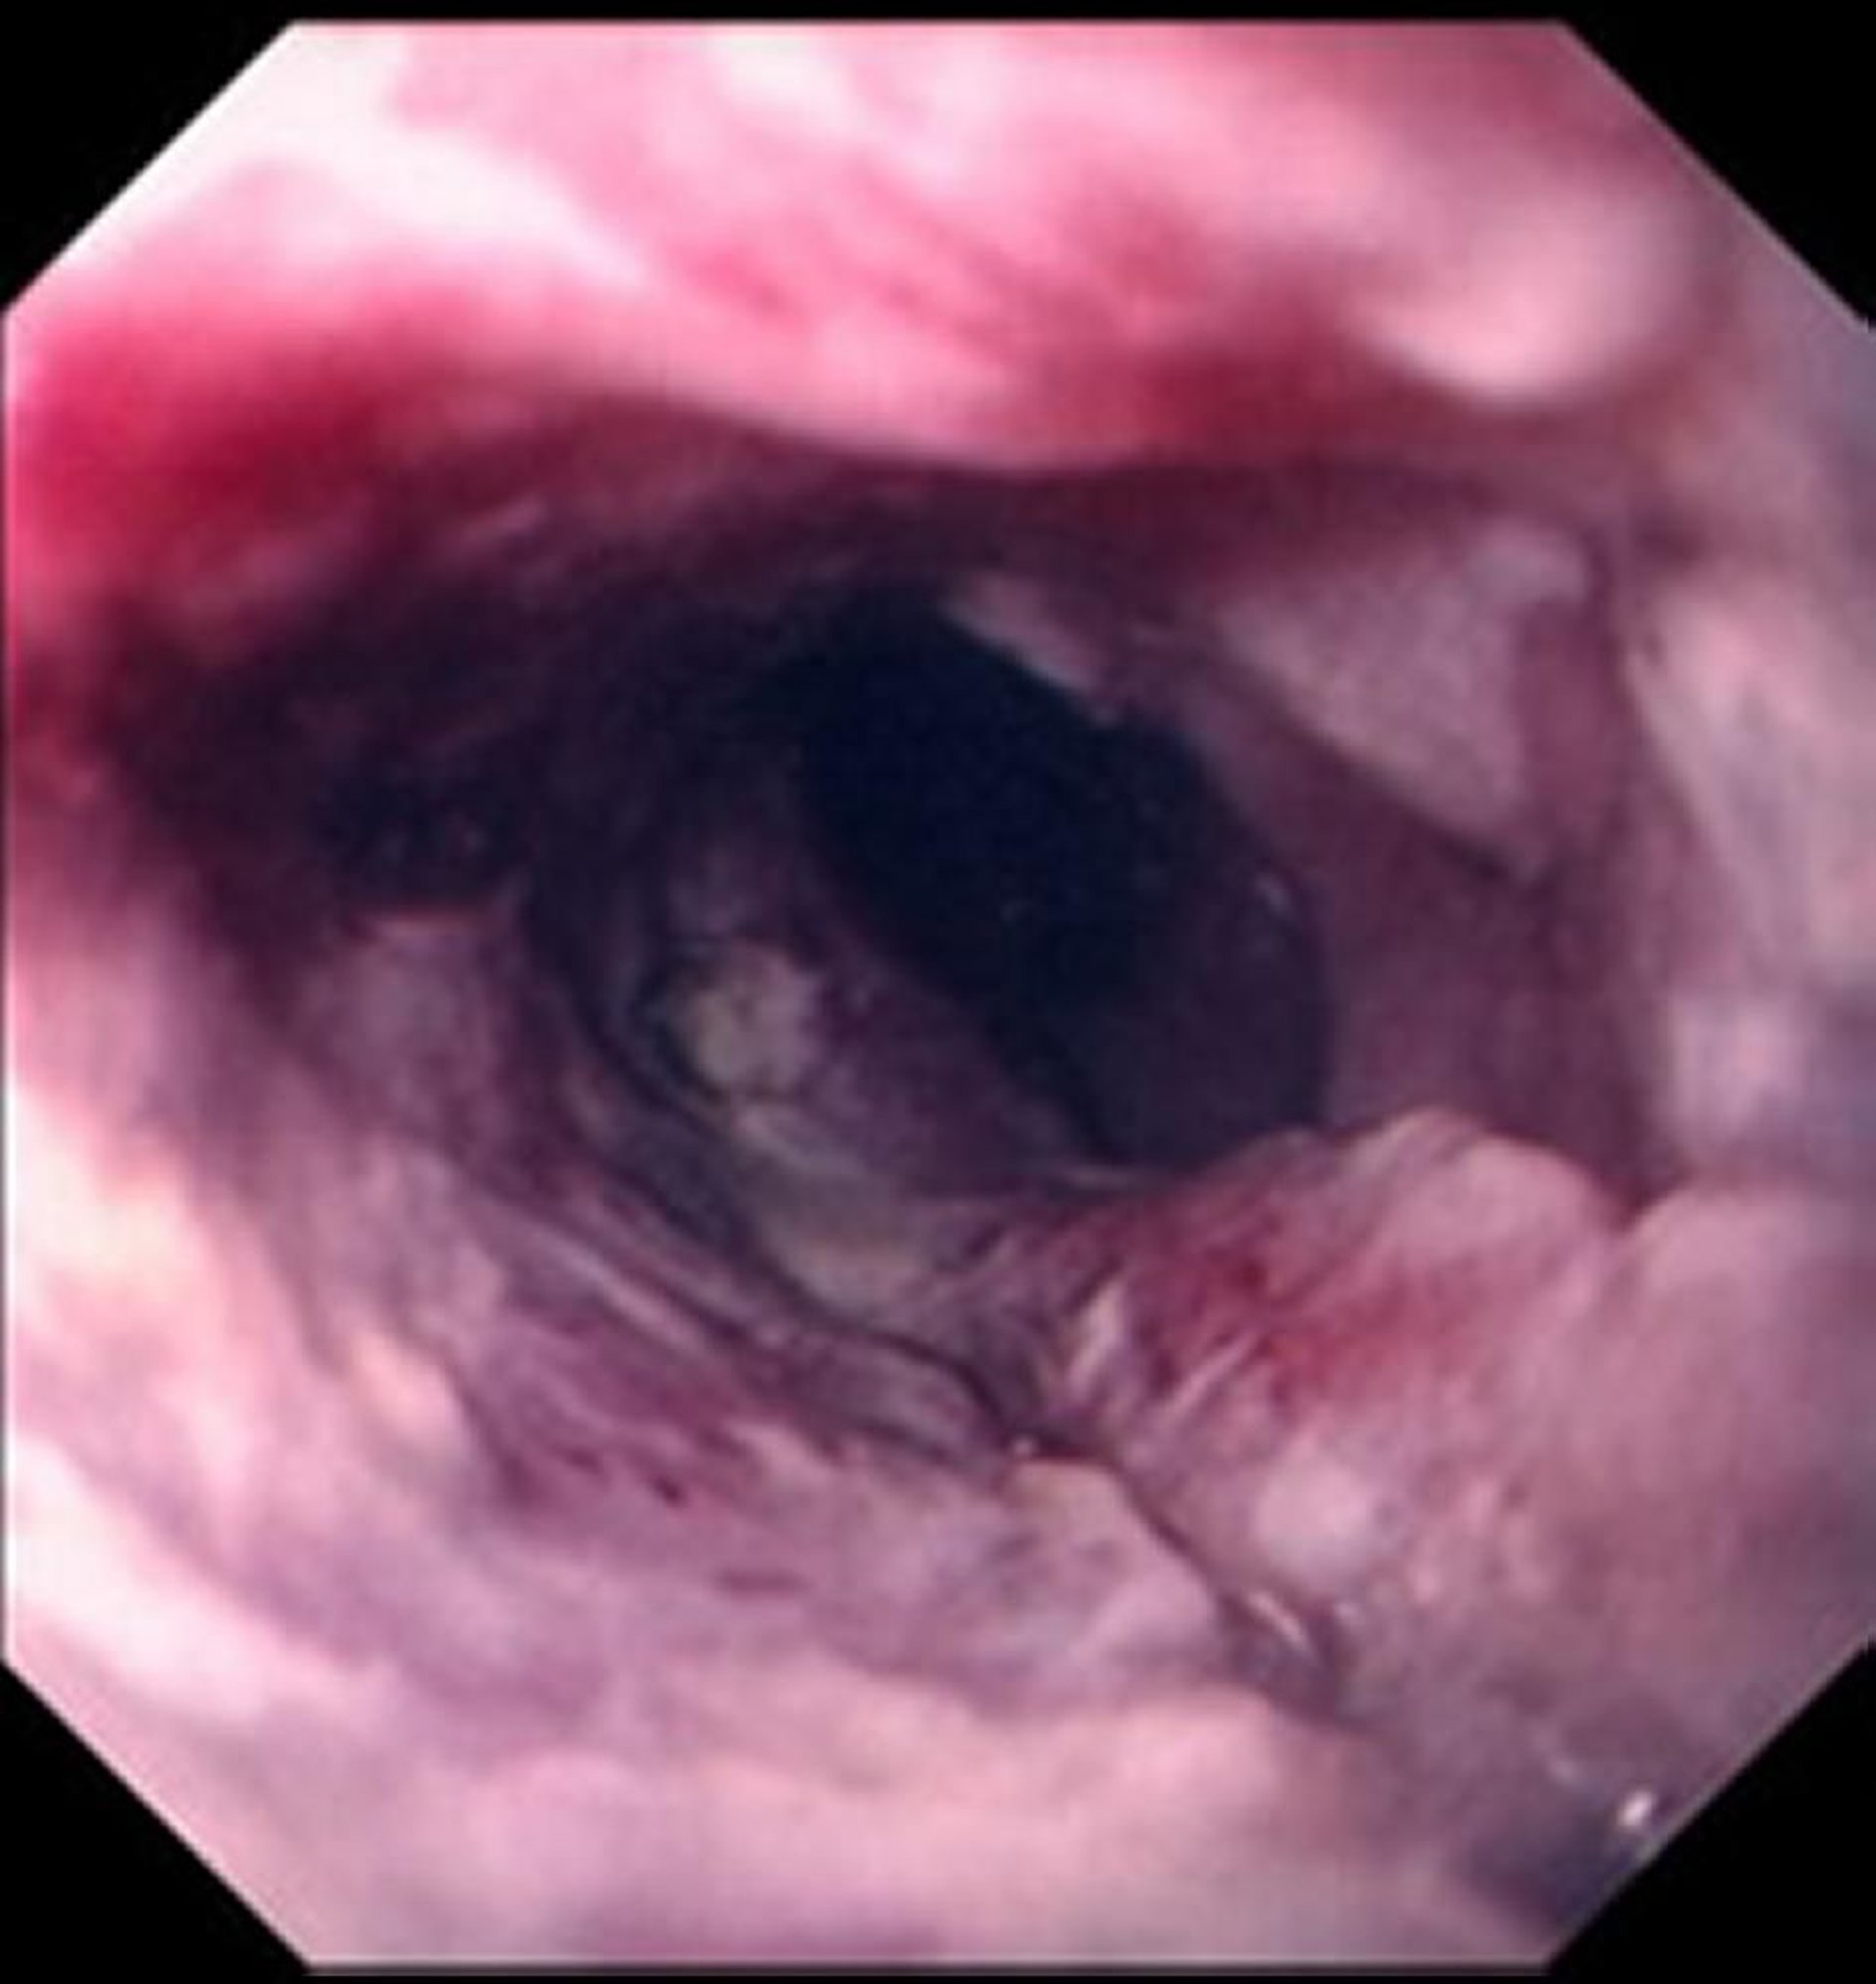

Plattenepithelkarzinom des Ösophagus

Plattenepithelkarzinome manifestieren sich typischerweise als ulzerierte, zerklüftete Masse, die das Lumen der Speiseröhre beeinträchtigt.

Images provided by David M. Martin, MD.